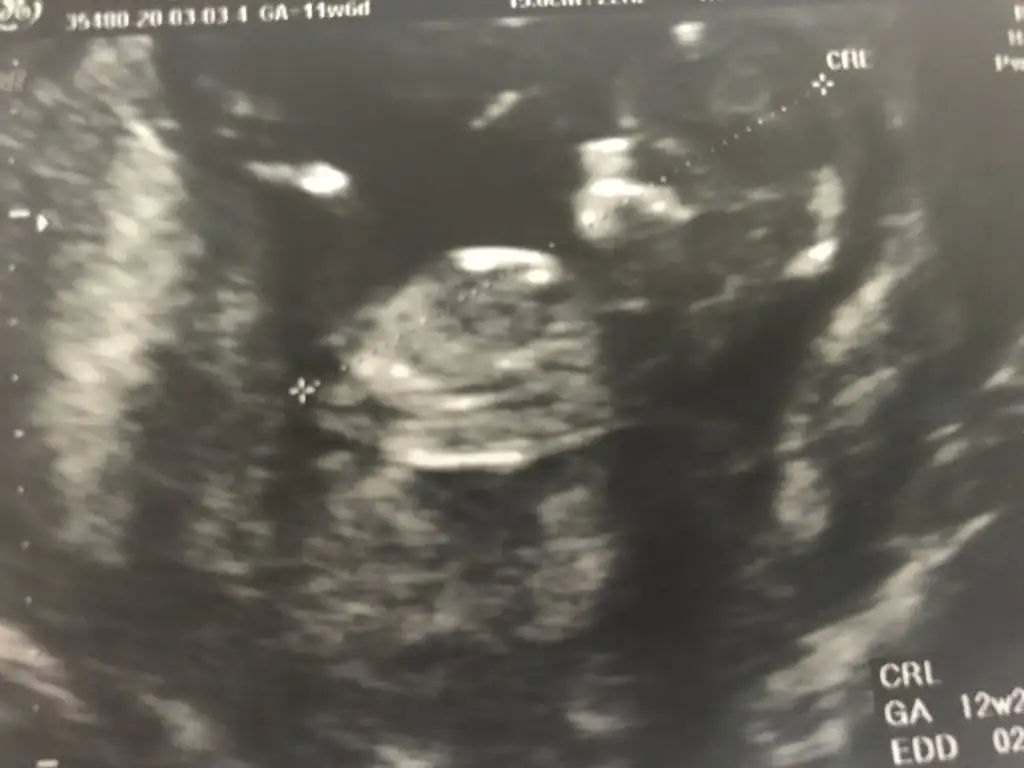

akadaşlar merhaba, ultrason görüntülerini paylaşsam bakabilir misiz.? meraktan çatlıyor insan 😍

Ultrason görüntülerimiz😍

yaa 😍 bende kız diye gördüm ama emin olamadım. bu nub teorisi inşallah doğrudur 😂 allah gönlümüze göre versin 😊 senin bebişin cinsiyeti kesinleşti mi peki

Yok canım 14 de gittim giremedi kemik.yapısı kız dedi ama kordon un arkasında bir şey de var sanki dedi ogrenemdim inşaallah bu teori doğrudur da kız olur 😂😂